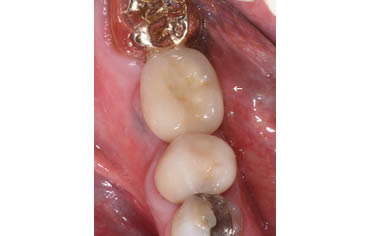

More back teeth replaced by dental implants

Case Three (2 images)

Case Four (4 images)

Case Five (4 images)

Case Six (8 images)

Case Seven (4 images)